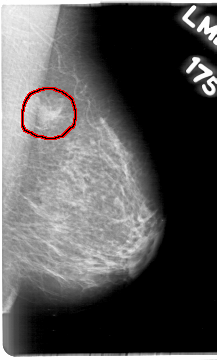

D_4016_1.RIGHT_MLO

LEFT_MLO LINES 5386 PIXELS_PER_LINE 3241 BITS_PER_PIXEL 12 RESOLUTION 43.5 OVERLAY

FILE: D_4016_1.LEFT_MLO.OVERLAY

TOTAL_ABNORMALITIES 1

ABNORMALITY 1

LESION_TYPE MASS SHAPE IRREGULAR MARGINS ILL_DEFINED

ASSESSMENT 0

SUBTLETY 5

PATHOLOGY BENIGN

TOTAL_OUTLINES 1

BOUNDARY